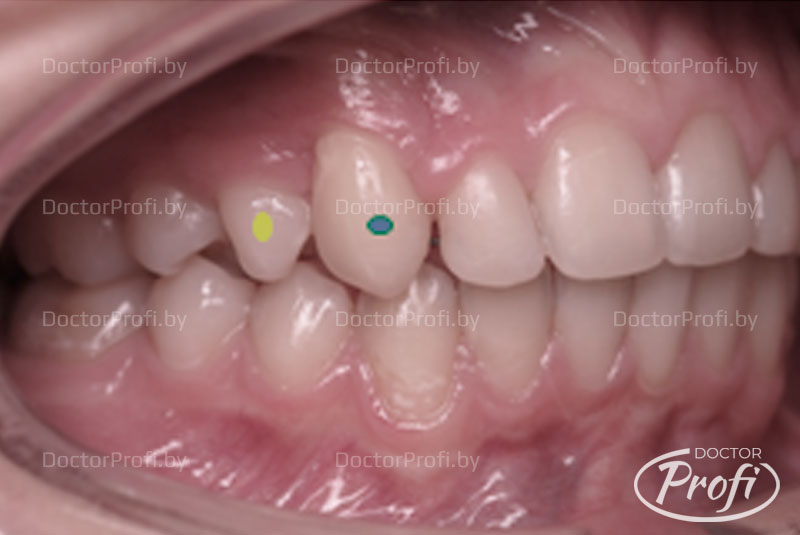

Результат:

В результате проведенного лечения мы получили возвращение зубов (клыка 1.3 и премоляра 1.4) на свои места и хорошее функциональное и эстетическое состояние. Лечение брекет-системой помогло обрести красивую улыбку и симметрию лица.

При ортодонтическом лечении мы всегда делаем фотографии, чтобы можно было увидеть результат работы и сравнить с тем, что было до.

Фотографии до и окончательный результат лечения вы можете увидеть ниже.